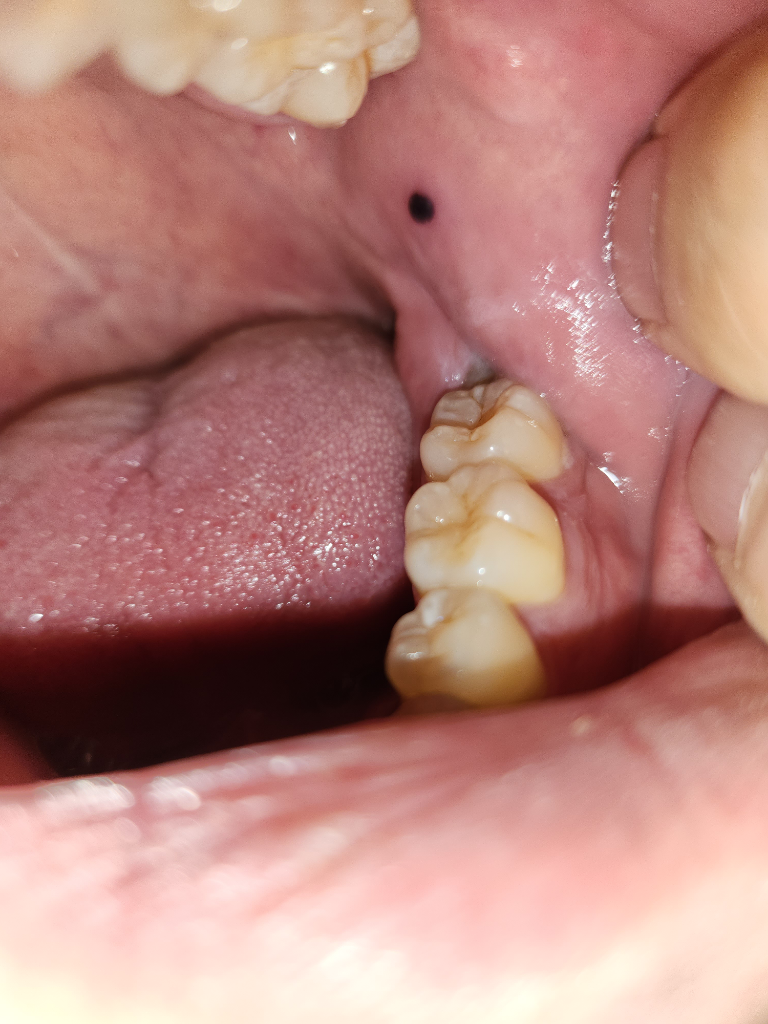

사진으로 보이는 증상은 혈종으로 보입니다 혈조는 점막 조직 내부에 자극으로 인해서 출혈이 된 다음에 점막 조직 안에 혈액이 남아 있는 것을 의미합니다.

크게 문제가 되진 않지만 너무 치아를 강하게 사용하다 보면 연조직에 자극이 되어 생길 수 있기 때문에 치아를 사용하는 강도를 줄여 주는 것이 좋습니다 자세한 확인을 위해서 치과에서 진료를 받아 보세요.

아마도 볼을 세게 깨물어서 생긴 것으로 보입니다. 크기가 더 커지거나 통증이 심해진다면 치과 가보시는 게 좋겠습니다.